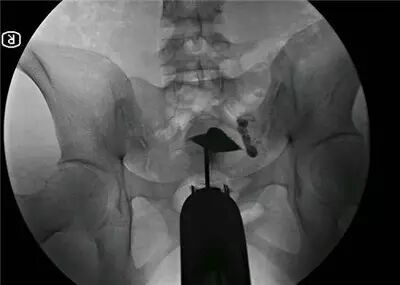

目前对输卵管堵塞部位、程度最准确的检查方法,仍是输卵管造影,一般在月经完结后的3-7天做检查。

输卵管造影结果:肠壁与子宫广泛粘连,右侧输卵管伞端粘连偏离卵巢,左侧输卵管卵巢与肠壁粘连。这样的粘连,不做手术不可能消失